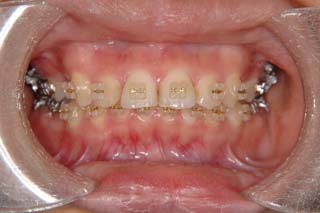

使用した主な装置名:TPB、マルチブラケット装置、歯科矯正用アンカースクリュー

リスク、副作用:抜歯によるリスク、マルチブラケット治療に伴う歯根吸収など偶発症が発生するリスクがある。

かなり強い上顎前突を示します。その他の問題はなさそうですが、小臼歯抜歯だけでは上顎前突に対応しきれそうにありません。上顎大臼歯に最大限の固定が必要と考えられましたので、上顎左右の臼歯部に計2本の歯科矯正用アンカースクリューの植立を検討してみました。

歯科矯正用アンカースクリューはそもそも骨の手術に使われる材料でしたが、使用目的を逸脱して矯正に利用されるようになってきました。しかし、現在では、治療効果が認められるようになり、自由診療だけでなく、保険診療でも使用が可能となっています。